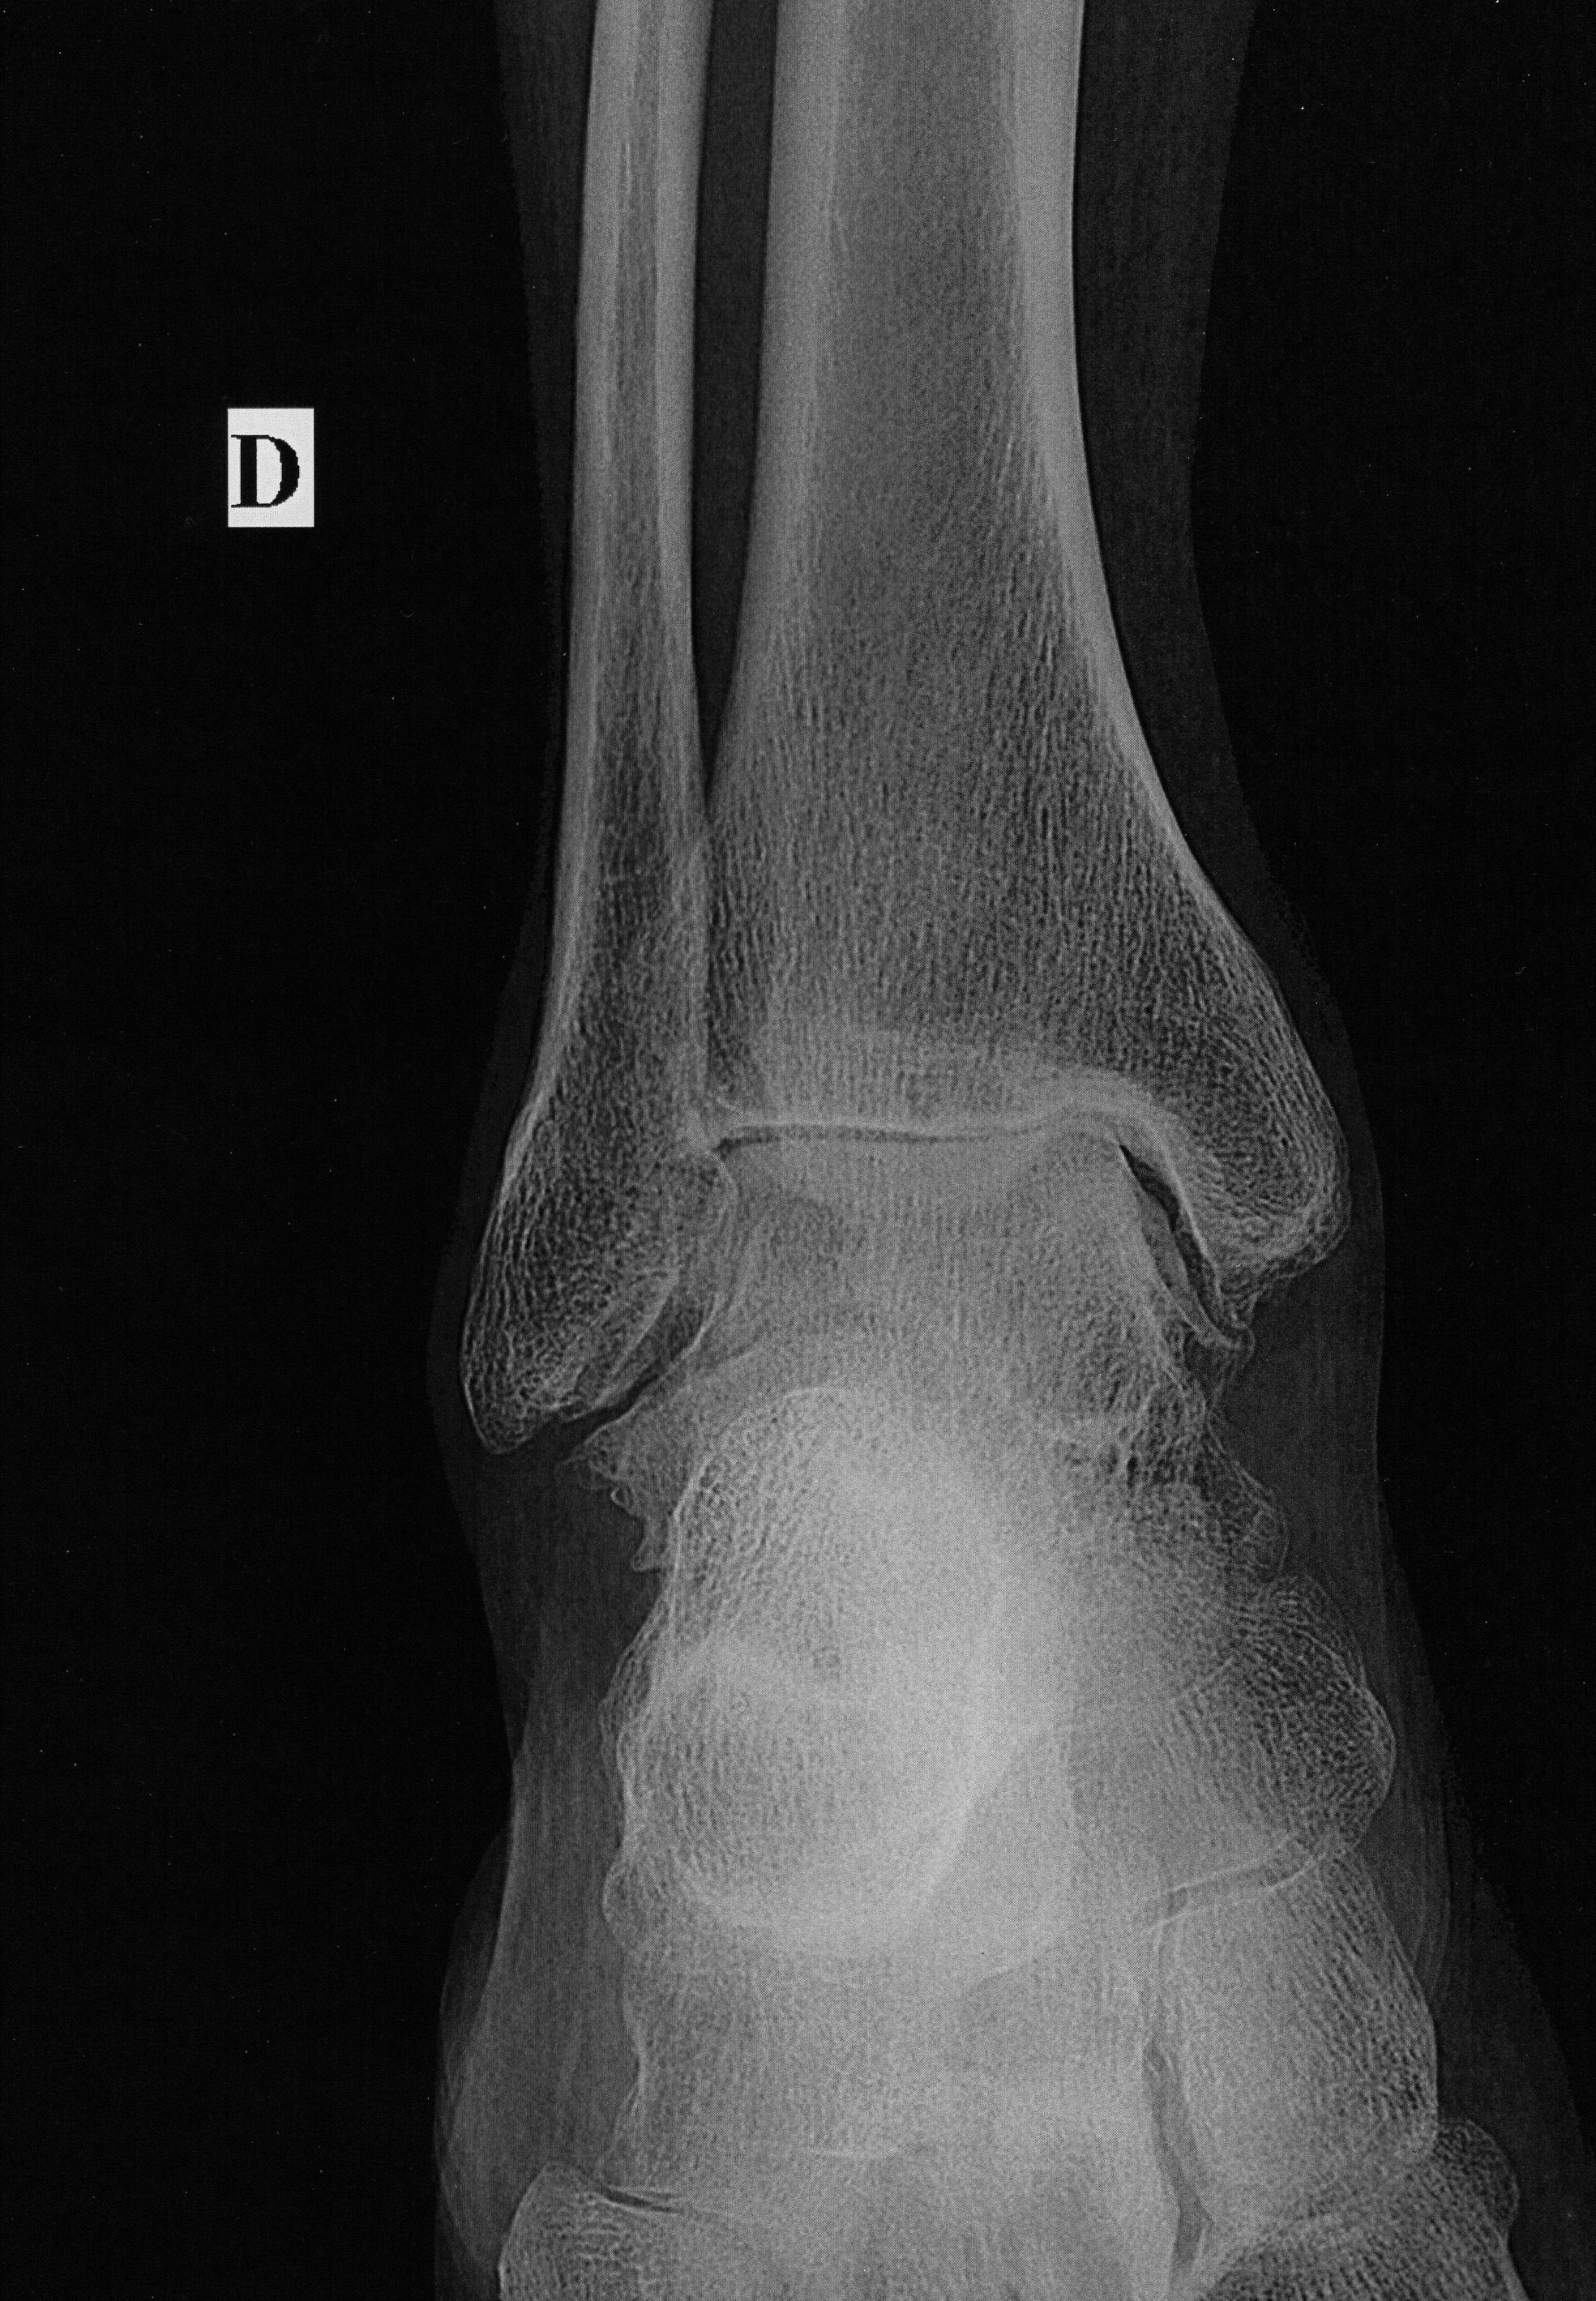

Avant...Aprés (vue de face)

Cliquer sur la photo